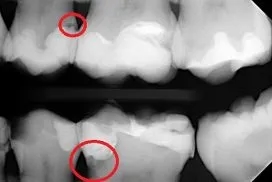

Próchnica na zdjęciu RTG objawia się jako ciemniejsze obszary w strukturze zęba. Te miejsca wskazują na ubytki w tkance twardej, które mogą być niewidoczne podczas standardowego badania. W zależności od stopnia zaawansowania, próchnica może dotyczyć szkliwa, zębiny, a nawet korzenia.

Główne objawy próchnicy na RTG to:

- Ciemne plamy w obrębie korony zęba, zwłaszcza między zębami.

- Ubytki w strukturze szkliwa lub zębiny.

- Zmiany w okolicy korzenia, które mogą wskazywać na infekcję.

- Nieregularne krawędzie zęba, sugerujące postępującą próchnicę.